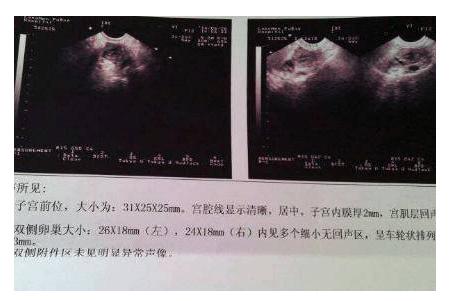

是不是准妈妈们从怀孕初期就开始期待孕子里的孩子是男是女了?因为国家

并不提倡鉴定胎儿性别,所以宝妈们对肚子里的宝宝究竟是男是女有着很大

的好奇心。在这里小编就教大家一个利用B超单上的数据来看男女的方法,

来一解准妈妈们的好奇心。